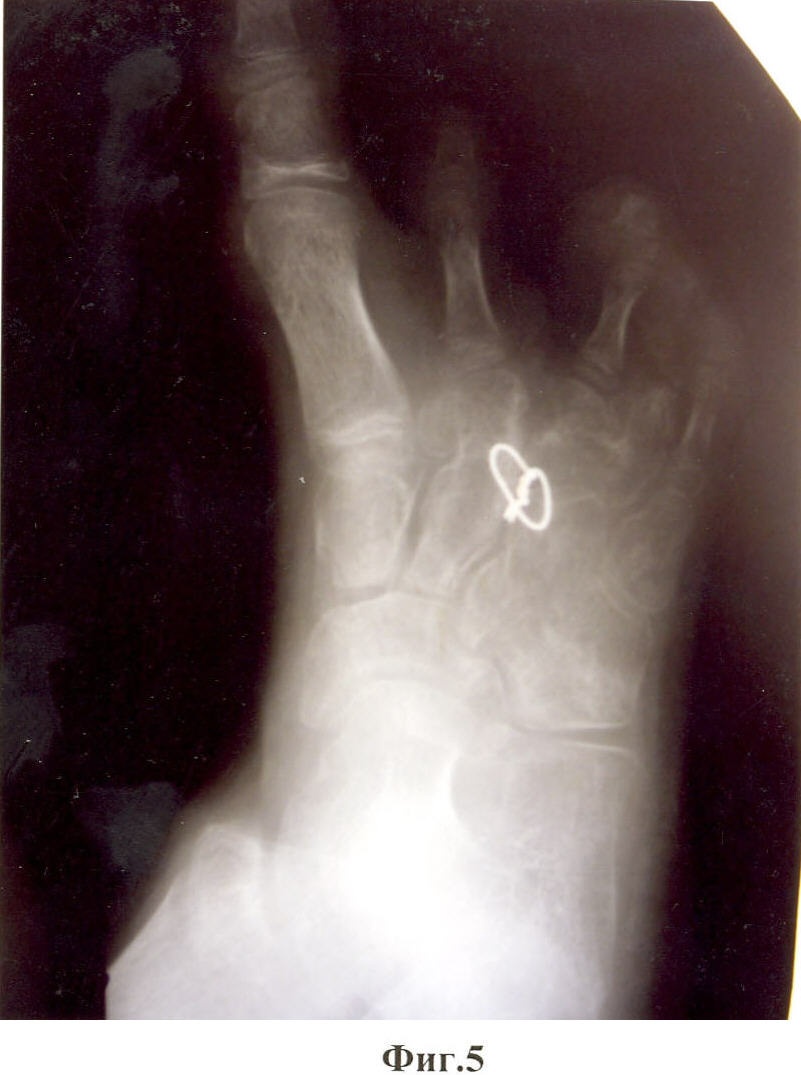

Предложенный способ иллюстрируют приведенные рентгенограммы и фотографии, где на фиг.1, 2 показан вид стопы до операции; на фиг.3, 4 – вид после операции; на фиг.5, 6 – снимок и фотография стопы через два месяца после операции.

Больной М-в, 12 лет. История болезни №6618. 11.12.2006 г. Поступил в отделение кисти «НИЦТ ВТО» с диагнозом: Сложное врожденное расщепление с элементами полидактилии, синостозом IV-V плюсневых костей и сверхкомплектом лучей обеих стоп (фиг.1, фиг.2).

21.12.2006 г. – больному была проведена операция по разработанной методике на правой стопе. Наркоз. Из разрезов по тыльной и подошвенной сторонам иссечены края расщелины стопы. С тыльного доступа удален III луч. Основание луча, прилегающее к II клиновидной кости, оставлено в виде костного фрагмента. Острым долотом с медиальной стороны кубовидной кости, ближе к основанию, поперечно длиннику стопы выбит костный клин, угол которого соответствует углу отклонения наружной половины расщепленной стопы от ее средней линии. Костный клин выбран так, что его вершина не доходит до наружного края кубовидной кости на 2-3 мм. Резецирован костный выступ по наружной стороне дистальной части II плюсневой кости. Через диафиз II плюсневой кости и дистальный отдел кубовидной кости поперечно с тыла на подошвенную сторону просверлены каналы. Через сформированные каналы проведена металлическая проволока так, чтобы концы ее вышли на тыл стопы. Обе половины расщепленной стопы с усилием смещены навстречу друг другу так, чтобы смежные стороны половин полностью сомкнулись. Концы проволоки с натяжением стянуты, скручены в узел и погружены в межкостную щель. Кожные швы до дренажей. Спиртовая повязка. Подошвенная гипсовая лонгета. Через две недели заживление раны первичным натяжением (фиг.3, фиг.4). Кожные швы сняты. Через 2 мес гипс снят. На контрольной рентгенограмме виден костный синостоз между фрагментом основания плюсневой кости и телом кубовидной кости (фиг.5, фиг.6). Больной начал нагружать правую стопу.